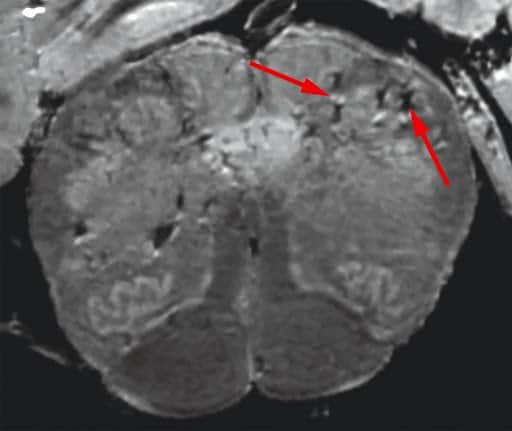

استخدم الباحثون في البداية جهاز تصوير بالرنين المغناطيسي (MRI) عالي القوة وأكثر حساسية بما يتراوح بين 4 و10 مرات من معظم الأجهزة العادية، لفحص عينات من البصيلات الشمية وجذع الدماغ لدى المرضى المتوفين بكوفيد-19. وقد كشفت عمليات المسح أن كلا المنطقتين بهما عدد كبير من البقع المضيئة والتي تشير غالباً إلى الالتهاب، والبقع الداكنة التي تمثل النزيف.

ثم فحص الباحثون بعد ذلك هذه البقع عن كثب تحت المجهر، ووجدوا أن البقع المضيئة تحتوي على أوعية دموية أرق من المعتاد وتُسرب في بعض الأحيان بروتينات الدم إلى الدماغ، وهو ما أدى على ما يبدو إلى حدوث استجابة مناعية. وفي المقابل، احتوت البقع الداكنة على أوعية دموية متخثرة ومُسربة لكنها لم تؤد إلى حدوث استجابة مناعية.